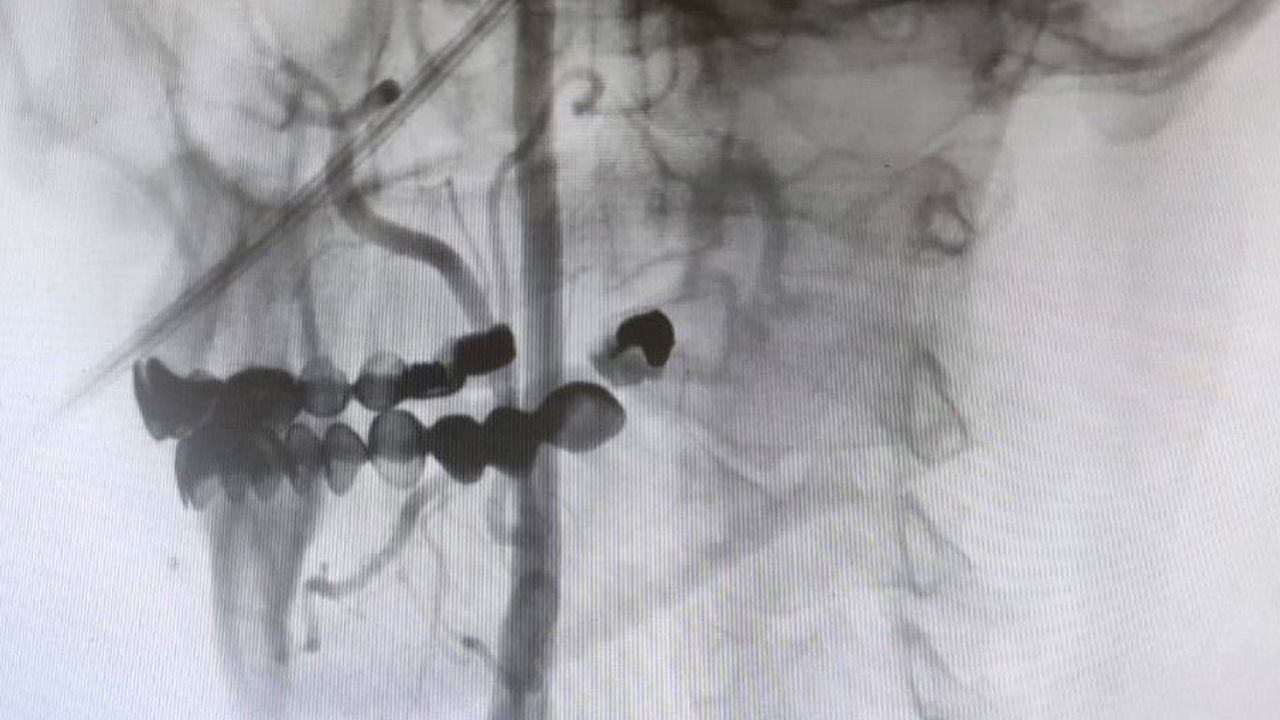

"Boyun damarlarını açma işlemi iki şekilde yapılabilir. Bir karotis endarterektomi dediğimiz ameliyatla bir diğer yöntem ise perkutan girişim dediğimiz stent yöntemiyle açılabilir. Biz kliniğimizde nöroloji ve kardiyoloji olarak bir konsey yapıyoruz. Damarı ciddi tıkalı olan ve buna bağlı felç geçirmiş hastalarda bu konseyde hastaya işlem yapıp yapmama kararı veriyoruz. Verdiğimiz karar çerçevesinde eğer hastaya işlem kararı vermişsek femoral arter dediğimiz kasık arterinden bir şitle 6 ya da 7 F çapında bir şitle ince bir boruyla bu damara giriş yapıyoruz ve boyun damarlarına ulaşıyoruz. Özellikle teller, filtreler ve stentlerle bu damarları açıp hastanın tedavisini gerçekleştiriyoruz. İşlem ameliyatsız olduğu için hastamız ertesi gün rahat bir şekilde problem olmazsa işlemde taburcu olabiliyor bu işlemden sonra. Bu işlemin yapılması için özellikle anjiografinin olduğu girişimsel nöroloji uzmanının ve girişimsel kardiyoloji uzmanının olduğu ve bu konuda yeterli vaka tecrübesine ve deneyime sahip uzmanların olduğu merkezler gerekir. Bunu yapabilmek için belli bir vaka sayısına ulaşmak ve bu konuda tecrübeli olmak gerekiyor. Biz de Manisa Şehir Hastanesi’ndeki girişimsel kardiyoloji ve nöroloji uzmanları olarak bu işlemi kliniğimizde efektif bir şekilde gerçekleştiriyoruz."